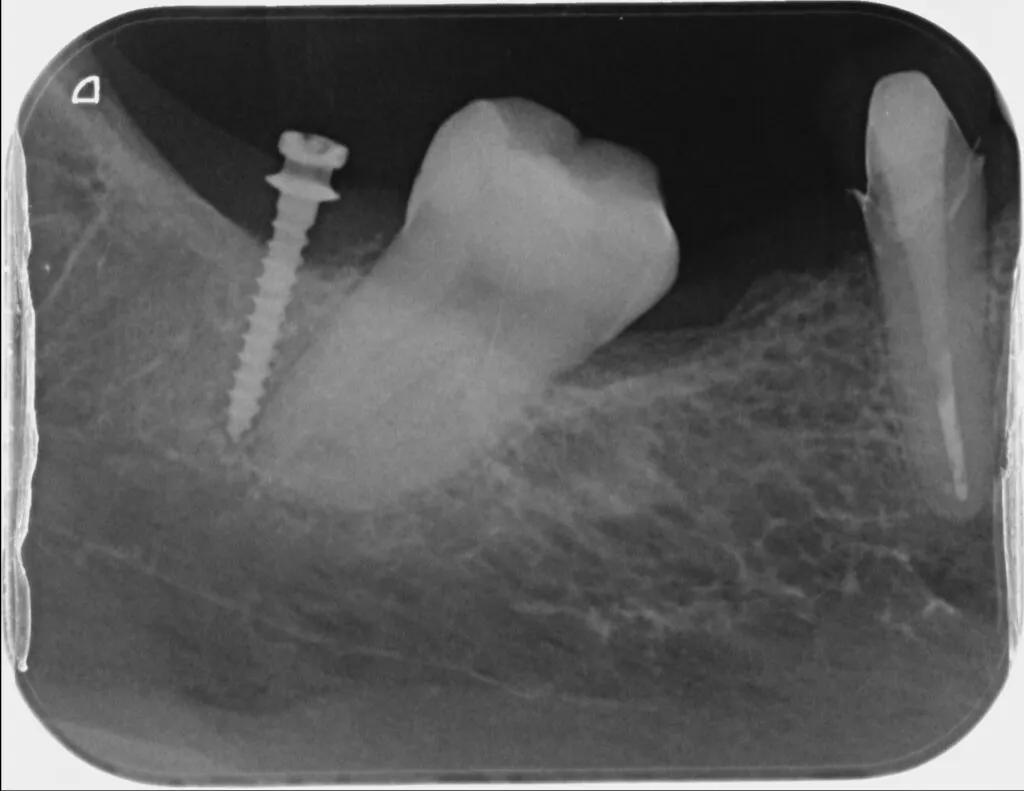

隙間があいている前歯を移動させる場合や、傾いている歯をまっすぐに修正する場合に有効な治療法です。またむし歯が骨の中まで進行した場合、通常は歯を抜くことになりますが、歯を引っ張りあげることで、保存できる場合もあります。